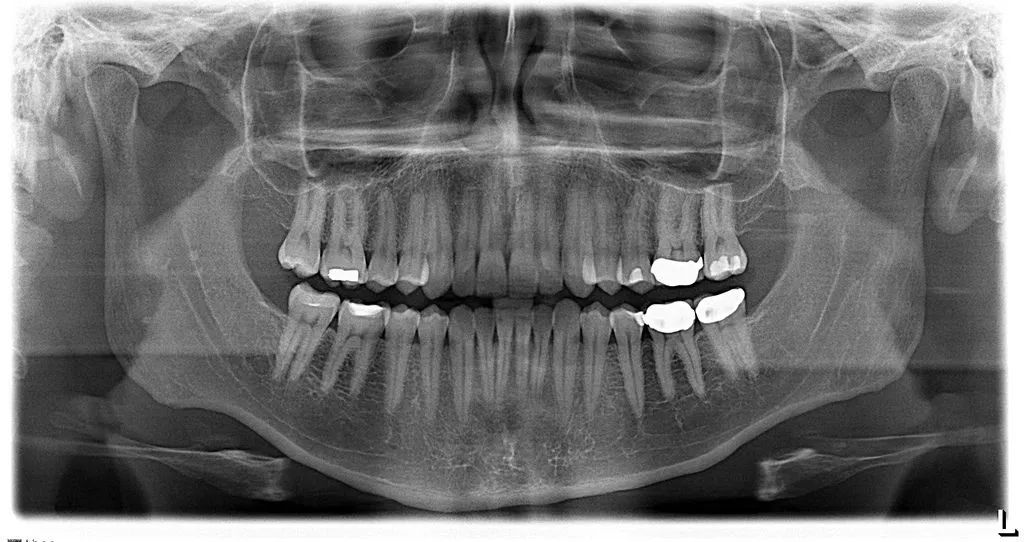

A panorex is a very impressive piece of imaging machinery in that it is capable of identifying many issues and structures that a normal x-ray is not. Initially you will sit in a chair with your chin on a small ledge. Once positioned in the machine, it will rotate around your entire head taking a full 360 degree view of the teeth, head, sinuses and bones.

The ability to view the full structure of your head as a whole is very informative to the dentist. It will allow us to see any potential problems and make sure that everything is functioning as it should be. The panorex is capable of viewing specific types of structural problems, infections or asymmetry among many others.

Digital x-rays are quickly becoming adopted by a large percentage of the dental industry. A digital x-ray allows the dentist to take an image of the tooth or teeth and put it into an imaging program. Within this imaging program, there are a number of tools that will allow the dentist to take a very close look at the teeth and surrounding structures with amazing accuracy. As a benefit to the patient, the digital x-ray also provides nearly 80% less radiation than a standard x-ray. This is due to the fact that the digital version of the x-ray is much more sensitive to this radiation and has been specifically designed with the patient in mind.